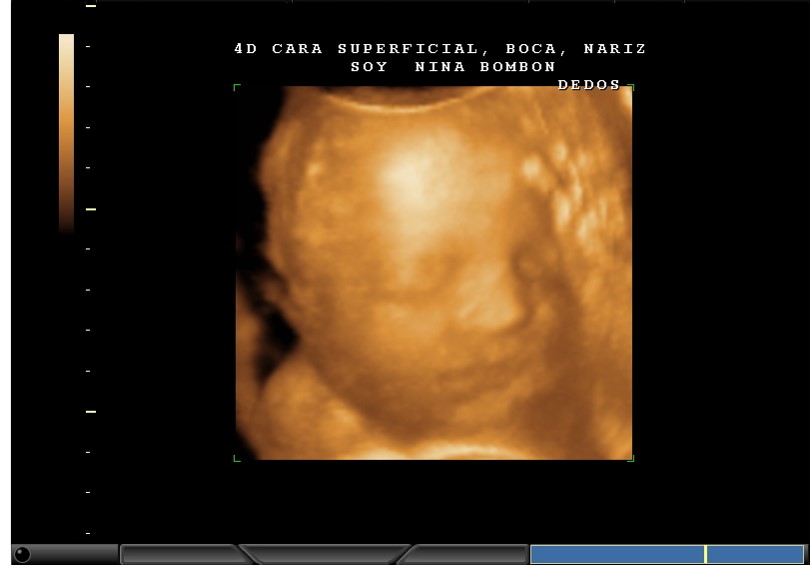

4D CARA IMAGEN CLARA, CARITA Y DEDOS

4D CARA SUPERFICIAL, BOCA, NARIZ, DEDOS